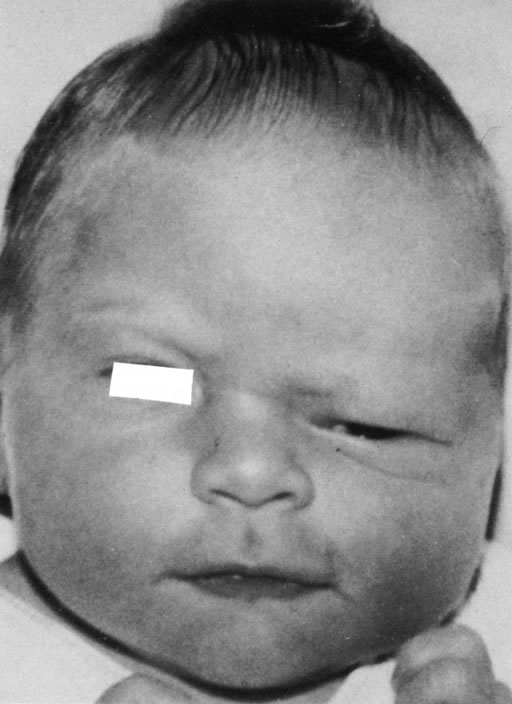

Anophthalmos and microphthalmos are usually unilateral and may be associated with a variety of craniofacial and systemic anomalies, including orbital hypoplasia, facial clefts, basal encephalocele, hemifacial microsomia, mandibulofacial dysostosis, cardiac anomalies, polydactyly, and mental retardation. When they occur unilaterally, they also can be associated with anomalies of the contralateral “normal” eye, including cataract, cornea1 opacities, microphthalmos, coloboma, epibulbar dermoids, and nystagmus. Anophthalmos and severe microphthalmos frequently are associated with contracted conjunctival fornices, phimotic eyelids, and generalized hypoplasia of the periocular soft tissues (Fig. 1). When soft tissue contractures occur, the early use of conformers is essential to expand these tissues.2 This treatment should be instituted in the first month of life, with progressive enlargement of the conformer over time to achieve maximum expansion of the conjunctival fornix. Unfortunately, this treatment usually does not stimulate adequate orbital bone growth, and unilateral microphthalmos and anophthalmos may be associated with secondary orbital hypoplasia (Fig. 2). Serial implantation of progressively larger orbital implants or placement of expansile orbital implants has been advocated to stimulate bony orbital development.3,4